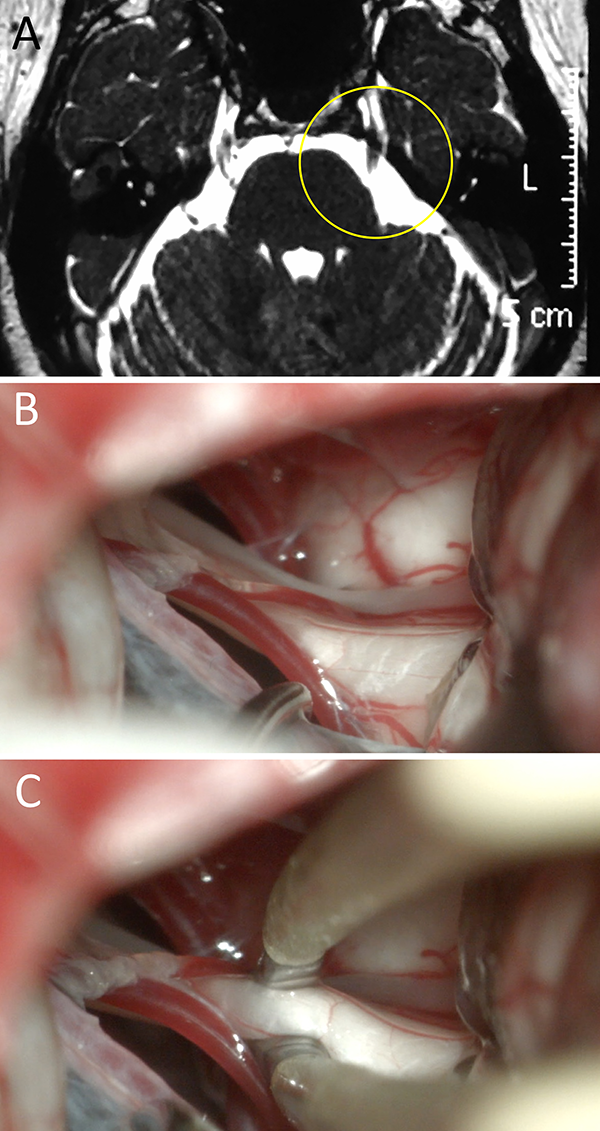

Figura 3:

Mujer de 37 años de edad con diagnóstico de NT atípica resistente a múltiples tratamientos (i.e. farmacológicos, termolesion). En RM actual se observó la presencia de CNV. Ante la persistencia del cuadro y la falta de respuesta a otros tratamientos, se decidió en Ateneo Médico el tratamiento mediante DNV. Durante la cirugía no se evidencio CNV alguno. La paciente evolucionó con mejoría parcial transitoria del dolor; actualmente en tratamiento con equipo de Medicina del Dolor. A) RM preoperatoria; B) hallazgo intraoperatorio; C) visión 360 sin conflicto. NT: neuralgia trigeminal; RM: resonancia magnética; CNV: conflicto neurovascular; DNV: descompresiva neurovascular.